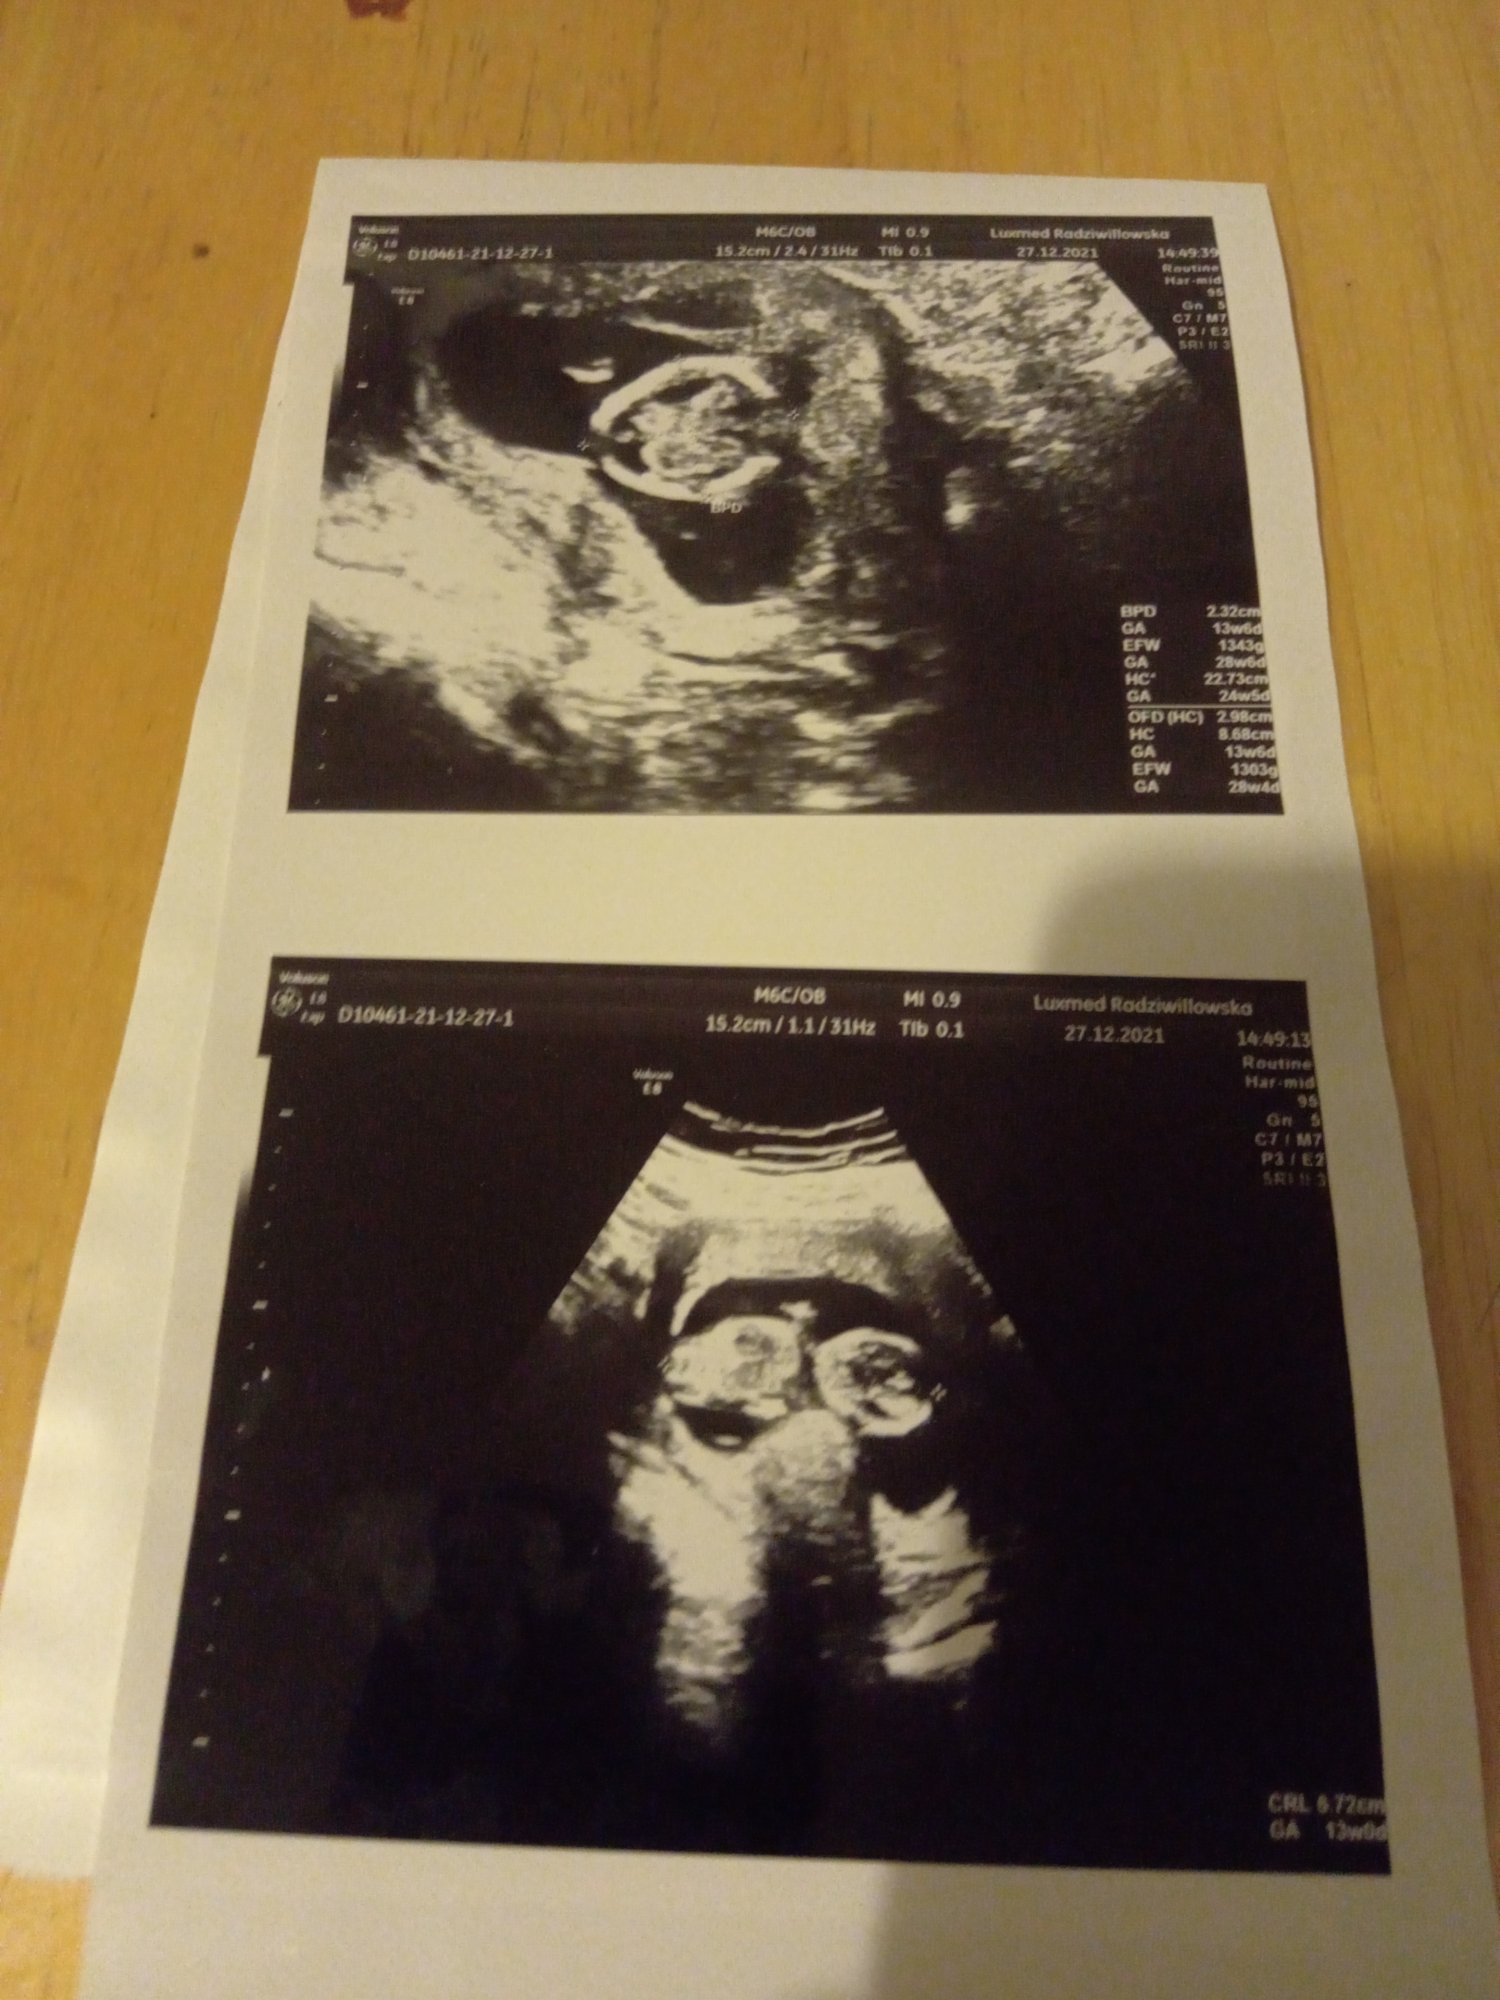

Witam jestem samotną matką wychowująca dwójkę dzieci . Spodziewam się córeczki jestem w 18 tygodniu ciąży moje problemy zaczęły się gdy miałam 18 lat i miałam wypadek samochodowy . Straciłam władzę w kręgosłupie ponieważ mam implanty w kręgosłupie piersiowym oraz przepuklinę krzyżowa. Dlatego też nie jestem wstanie pracować bo każdy wysiłek fizyczny to bardzo duży ból